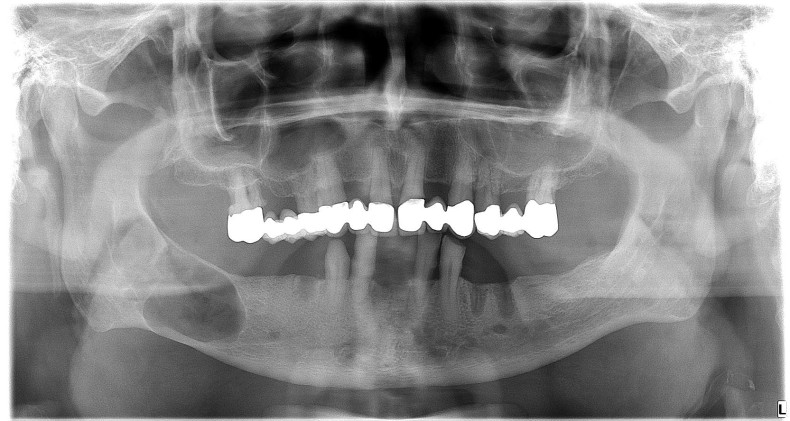

İnkşafı və böyüməsi tədricən baş verdiyindən, bu proses pasiyent tərəfindən demək olar ki hiss edilmir. Yalnız törəmənin ciddi ölçülərə çatması nəticəsində və ya iltihablanması nəticəsində meydana çıxan kliniki əlamətlər nəticəsində aşkarlanır. Əksər hallarda isə çəkilən diş və çənə rentgen şəkillərində təsadüfən rast gəlinir.

Törəmələrin müalicəsi onun növünə, yerləşməsinə, ölçüsünə, pasiyentin yaş və sağlamlıq durumuna görə seçilir və icra olunur. Müalicə prinsipi bütün hallarda nəticə etibarilə, törəmənin kənarlaşdırılmasına əsaslanır. Müalicə çox zaman yerli ağrısızlaşdırma altında bəzən isə (məsələn, böyük ölçülü kistlərin müalicəsində) ümumi ağrısızlaşdırma altında aparılır. Müalicənin gecikdirilməsi və ya təxirə salınması kistlərin daha da böyüməsinə, nəticədə ciddi miqdarda sümük itkisinə səbəb olur. Müalicənin natamam aparılması leziyonun yenidən təkrarlanmasına (residiv) səbəb ola bilir.